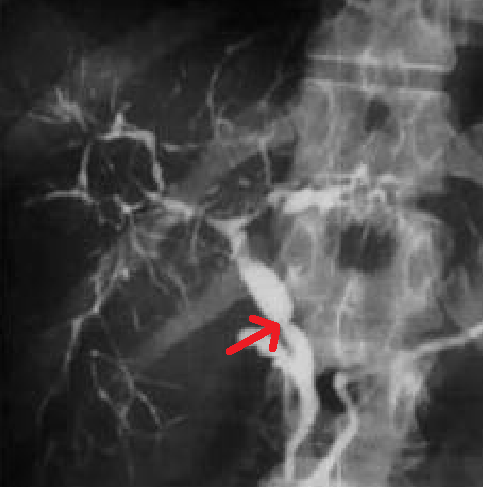

Рисунок 2. Стриктура холедоха (по данным МРХПГ)[1]

Наблюдается множество стриктур с мешковидными расширениями как внутрипеченочных, так и внепеченочных желчных протоков, что являются типичной холангиографической картиной. Стриктуры приводят к регионарному холестазу, очаговому перибилиарному фиброзу и в конечном итоге к холестатическому циррозу печени. Изолированное внутрипеченочное поражение встречается у 30% пациентов, а изолированное внепеченочное поражение встречается редко. Почти у 90% пациентов наблюдается аномалии желчного пузыря, а камни в желчных протоках обнаруживаются у 25% пациентов.

Рисунок 1. Патологические изменения желчевыводящих путей при первичном склерозирующем холангите (макроскопические изменения) [5].